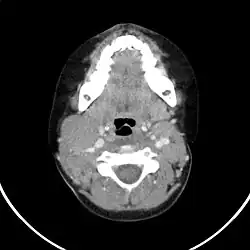

Für die genaue Stadieneinteilung sind weitere Untersuchungen notwendig:

- Röntgen-Thorax

- Sonographie des Bauchraums

- Computertomographie von Hals, Thorax und Abdomen

- Knochenmarkpunktion zur Gewinnung der Knochenmarkhistologie und Ausschluss eines Knochenmarkbefalls

Eine genaue Klassifizierung und Stadieneinteilung ist für eine gezielte Therapie unerlässlich.